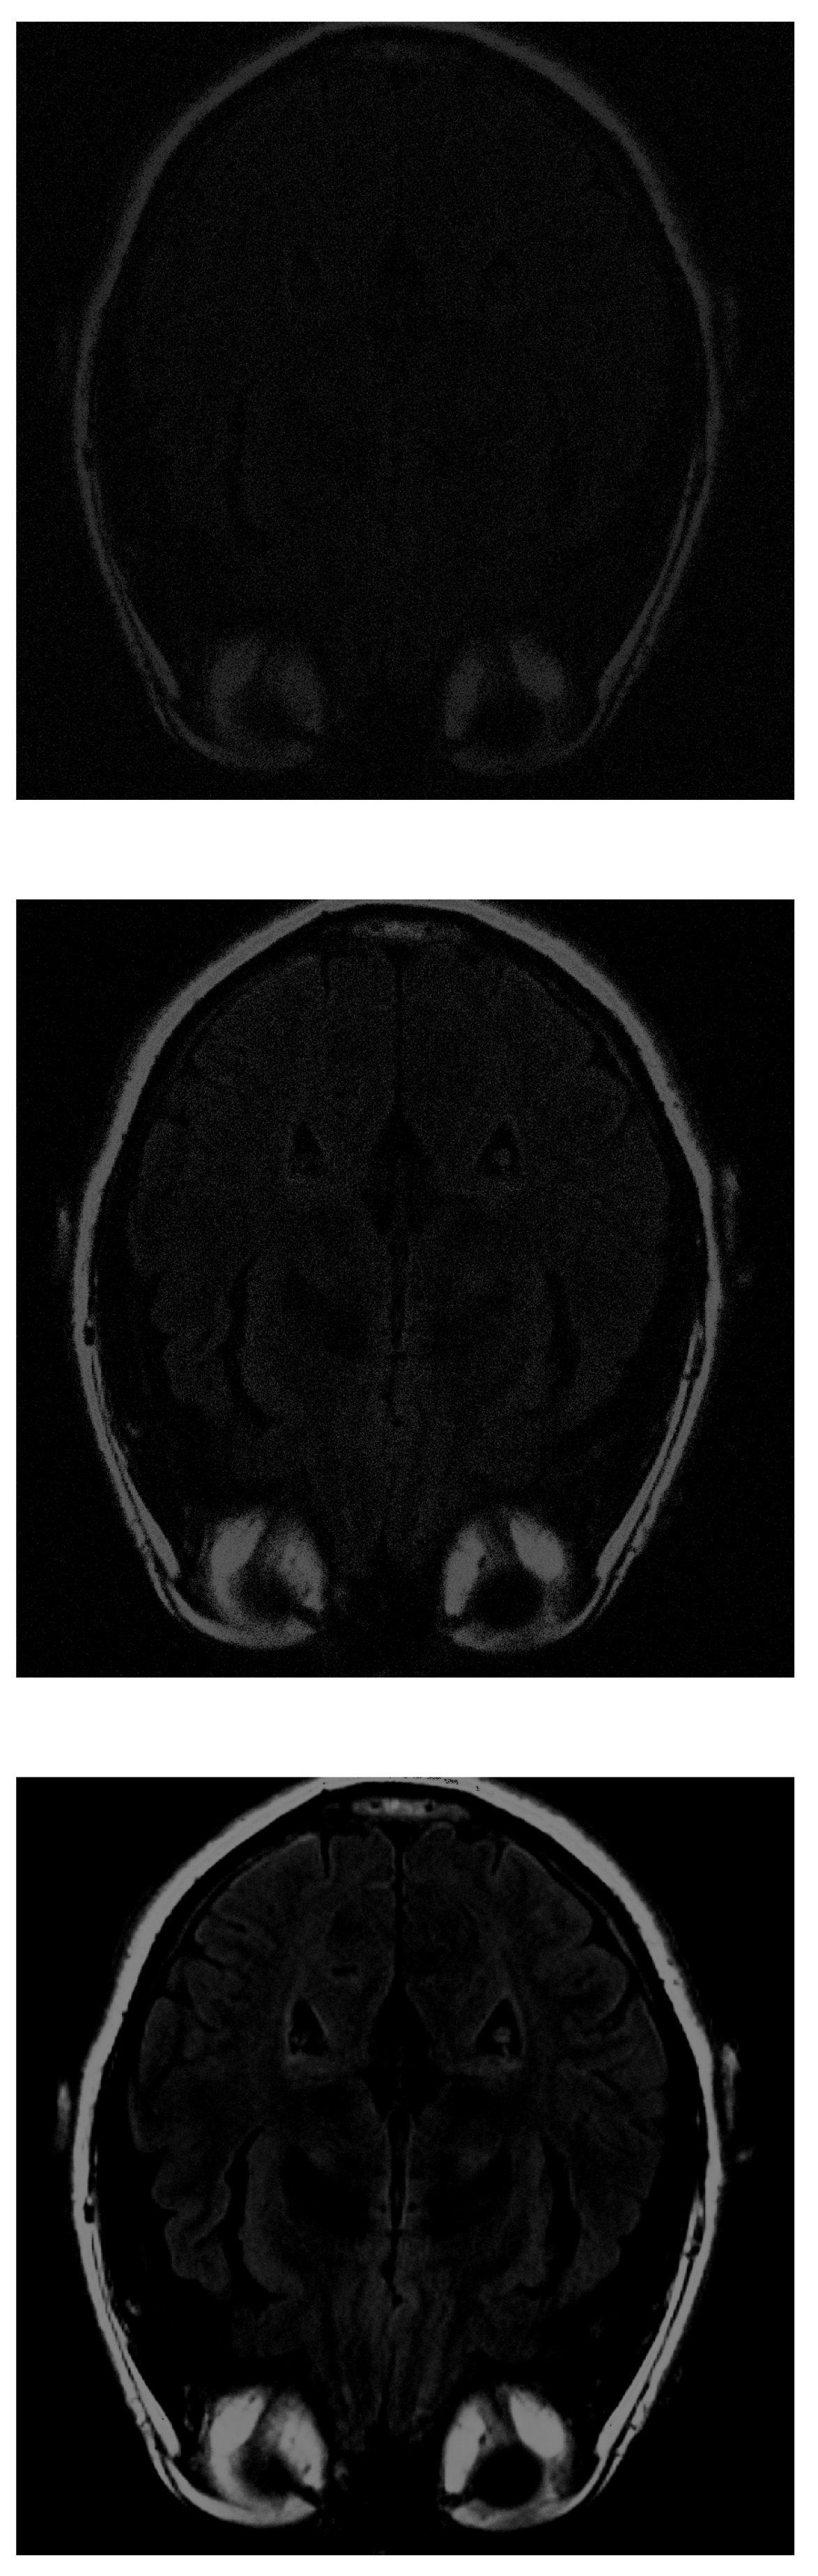

With the PD algorithm, the object is much clearer with lower measurements. With 30% of the initial values (Figure 8 top), the structure inside the head can be recognized and delimited, even if it is of low intensity. As the number of measurements increases, the images obtain better resolution. At 70% (Figure 8 middle), the image is similar to the original. Finally, at 100% (Figure 8 bottom), the gray matter loses its intensity.

Figure 8.

Reconstruction of the image in Figure 3 using PD with (top), (middle) and (bottom) of taken measurements.